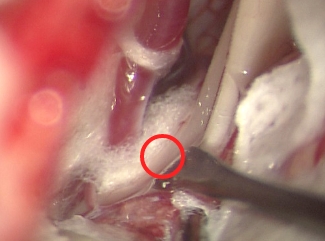

(写真3―前)顔面けいれんの患者さん(圧迫解除前)

この時点では、顔面神経は圧迫している血管の奥(緑矢印)で隠れてしまうため見えません。手前に見える神経は音を聞く聴神経で、手術により聴力が下がることもあることから、聴神経をはじめ周囲の構造に最大限の注意を払い、モニタを駆使して圧迫血管を少しずつ浮かせていきます。

(写真3―後)顔面けいれんの患者さん(圧迫解除後)

圧迫の取れた顔面神経がよく見えるようになります(赤丸が圧迫されていた場所)。三叉神経の場合と同じように、圧迫の原因となる血管は白く見えるテフロンの繊維で、ふたたび神経に当たらないように固定します。